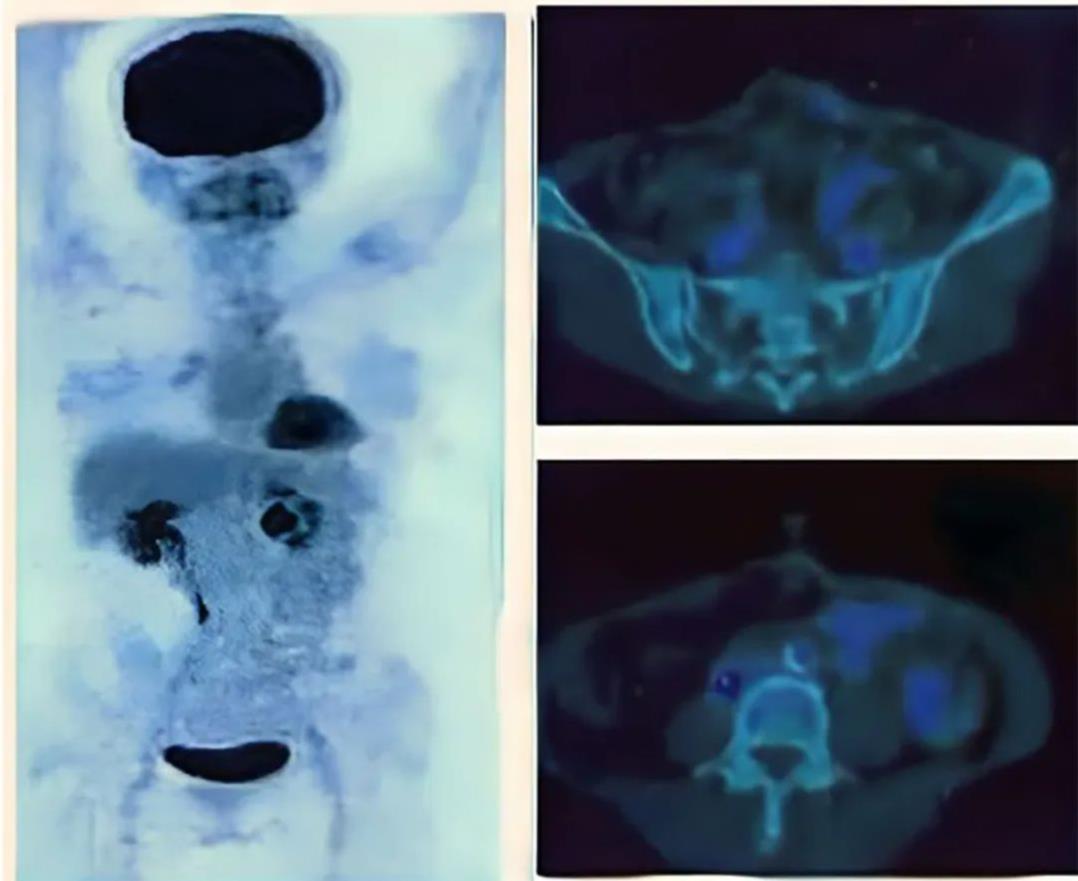

1、横结肠切除术后6个月,NK细胞治疗前:PET扫描显示,结肠系膜和腹膜区域淋巴结中,氟脱氧葡萄糖摄取阳性(详见下图,绿色箭头所指位置)。

▲图源“Cancer Rep”,版权归原作者所有,如无意中侵犯了知识产权,请联系我们删除